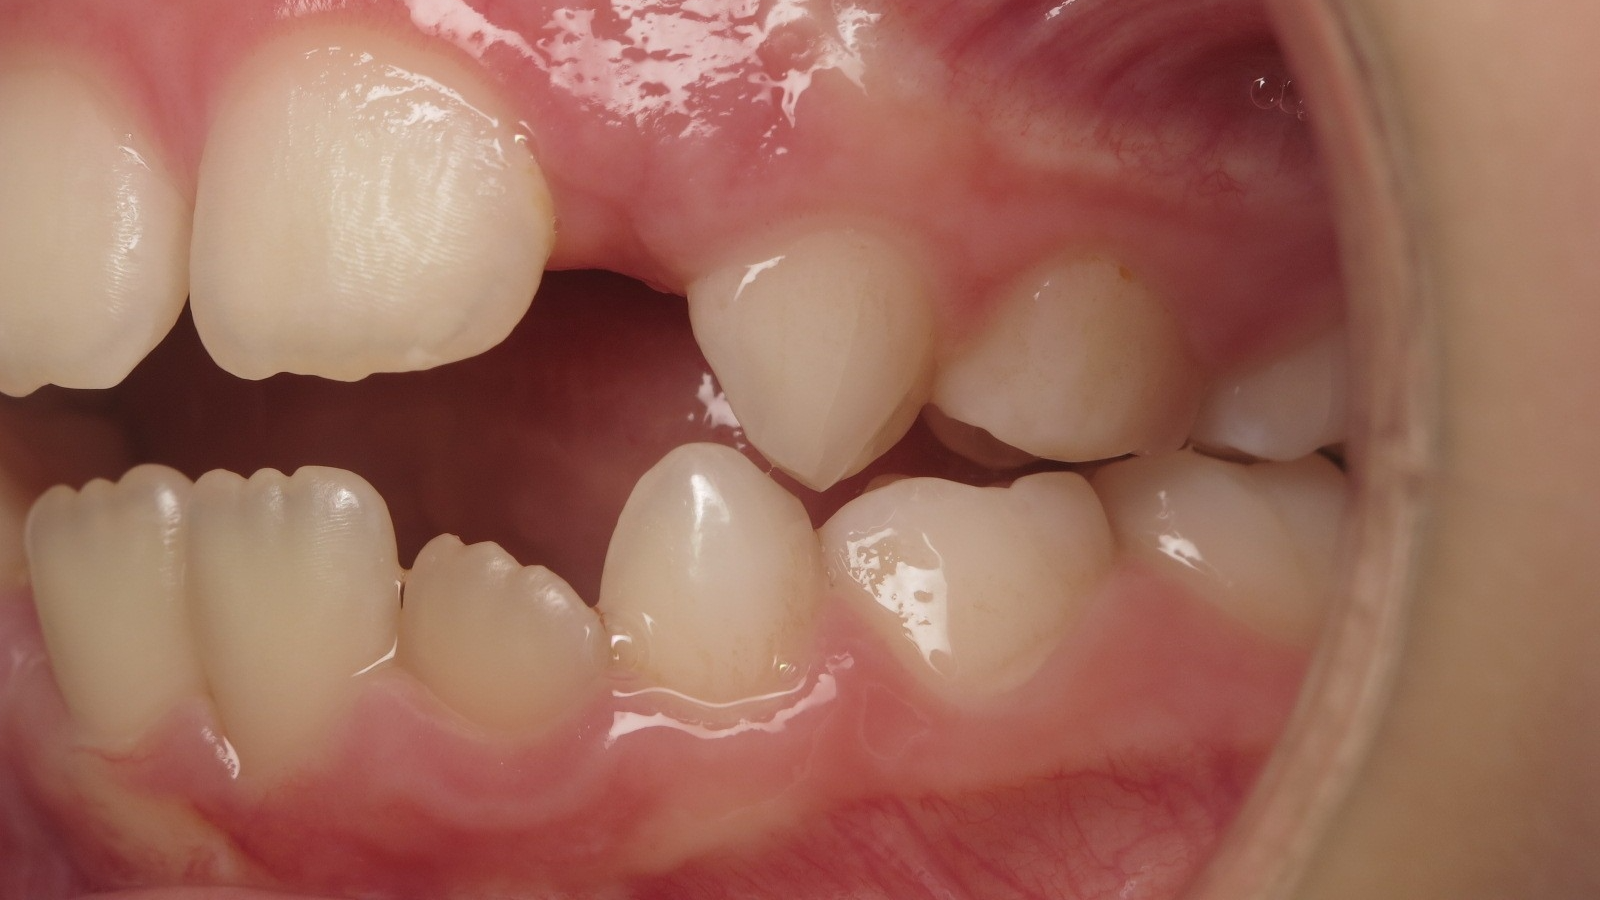

14 béance inversé gauche 5 ans

inversion postérieur coté droit et espace entre l'arcade du haut et du bas (béance)